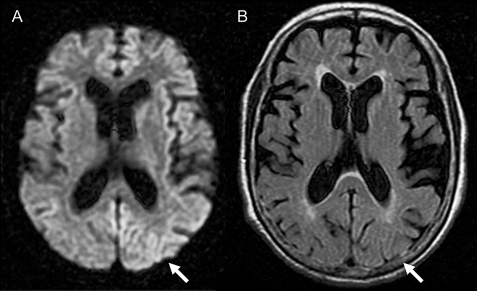

Get Creutzfeldt Jakob Disease Brain Mri Gif. It has severe effects on the brain. In the united states there are about 300 cases per year.

The Pulvinar Sign in Variant Creutzfeldt-Jakob Disease ... from jamanetwork.com